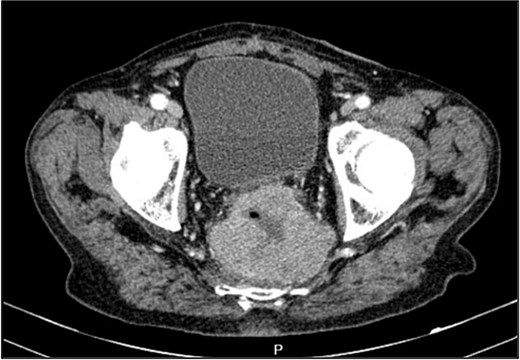

A contrast-enhanced chest-abdominal-pelvic computed tomography (CT) scan revealed a solid, multilobular mass, with approximately 8 × 6 × 8 cm, likely originating from the SB, with asymmetric wall thickening, heterogeneous contrast enhancement, areas consistent with necrosis and central calcification (Figs 1 and 2), suggestive of GIST. Simultaneously, a solid nodular lesion was identified on the anterior wall of the rectum, exhibiting exophytic growth with a heterogeneous texture, well-defined borders and measuring 5 × 3 cm, without adjacent fat infiltration, raising suspicion of another GIST (Fig. 3).